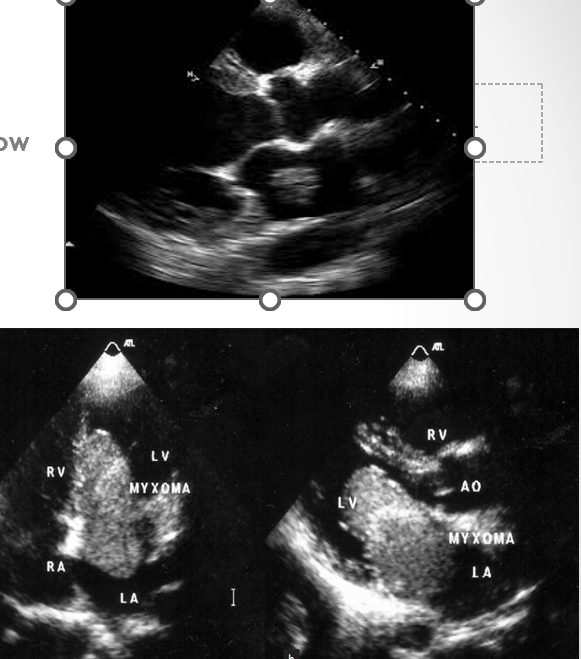

what is a myxoma?

non rheumatic form of mitral stenosis where tumor prolapses into mitral valve funnel in diastole and produces inflow obstruction